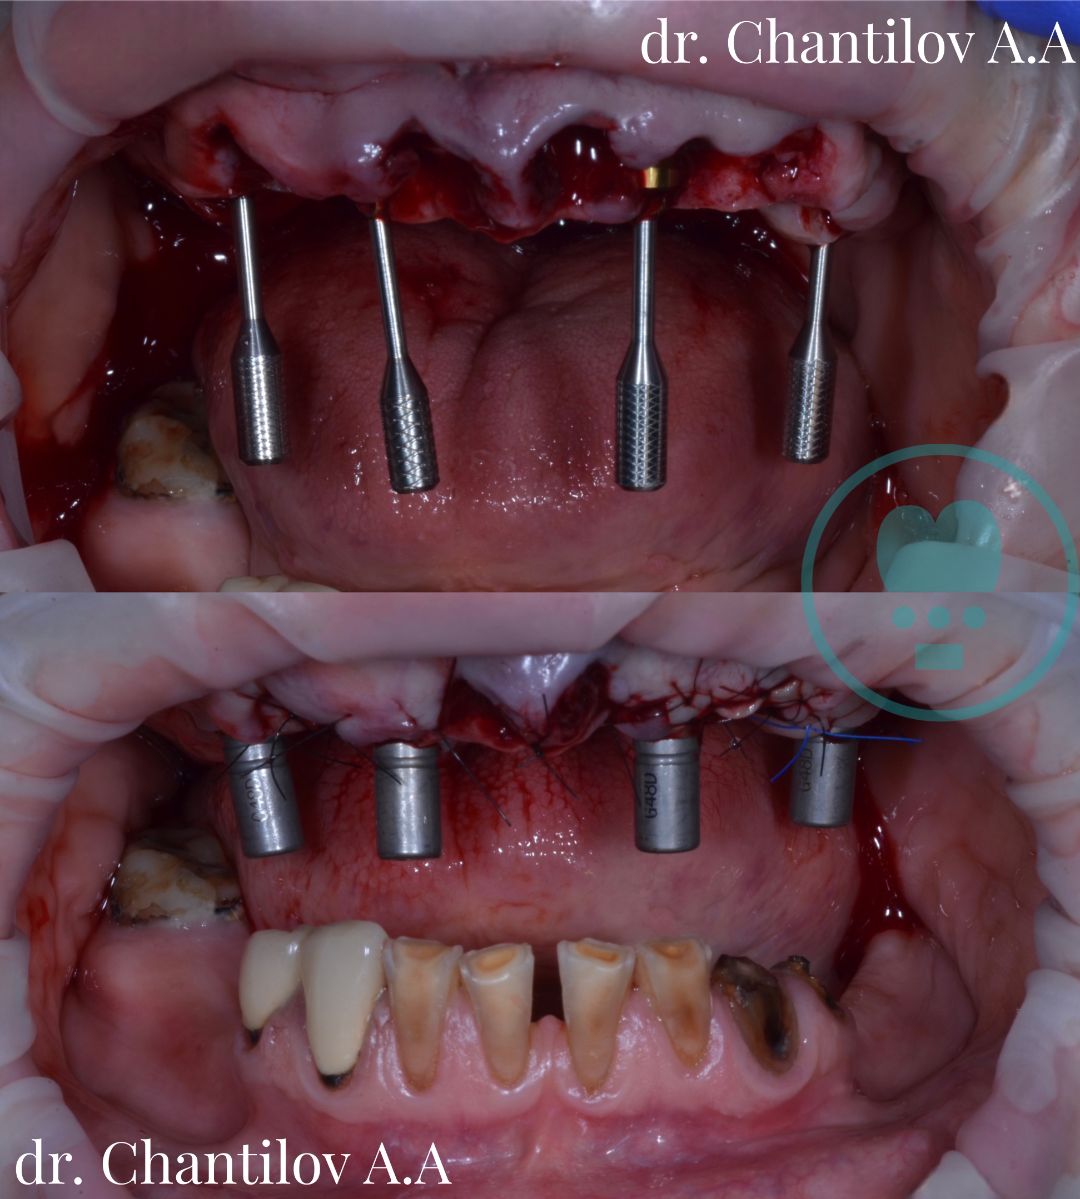

Имплантация зубов челюсти - фото до и после

Изготовление индивидуального шаблона